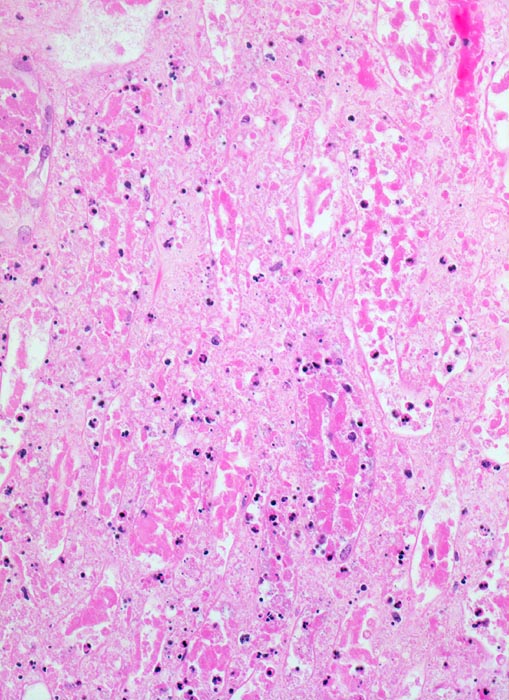

akuter Niereninfarkt: Koagulationsnekrose

Vollständig nekrotische Tubuli ohne erkennbare Zellkerne. Die Nekrose ist durchsetzt von zerfallenden neutrophilen Granulozyten. Die schwarzen Punkte entsprechen Kerntrümmern der Granulozyten.

Chronisches Vorhofflimmern mit Morbus embolicus: anämische Infarkte verschiedenen Alters in beiden Nieren und in der Milz. Alte abgebaute Enzephalomalazie im Versorgungsbereich der Arteria cerebri media rechts.

200